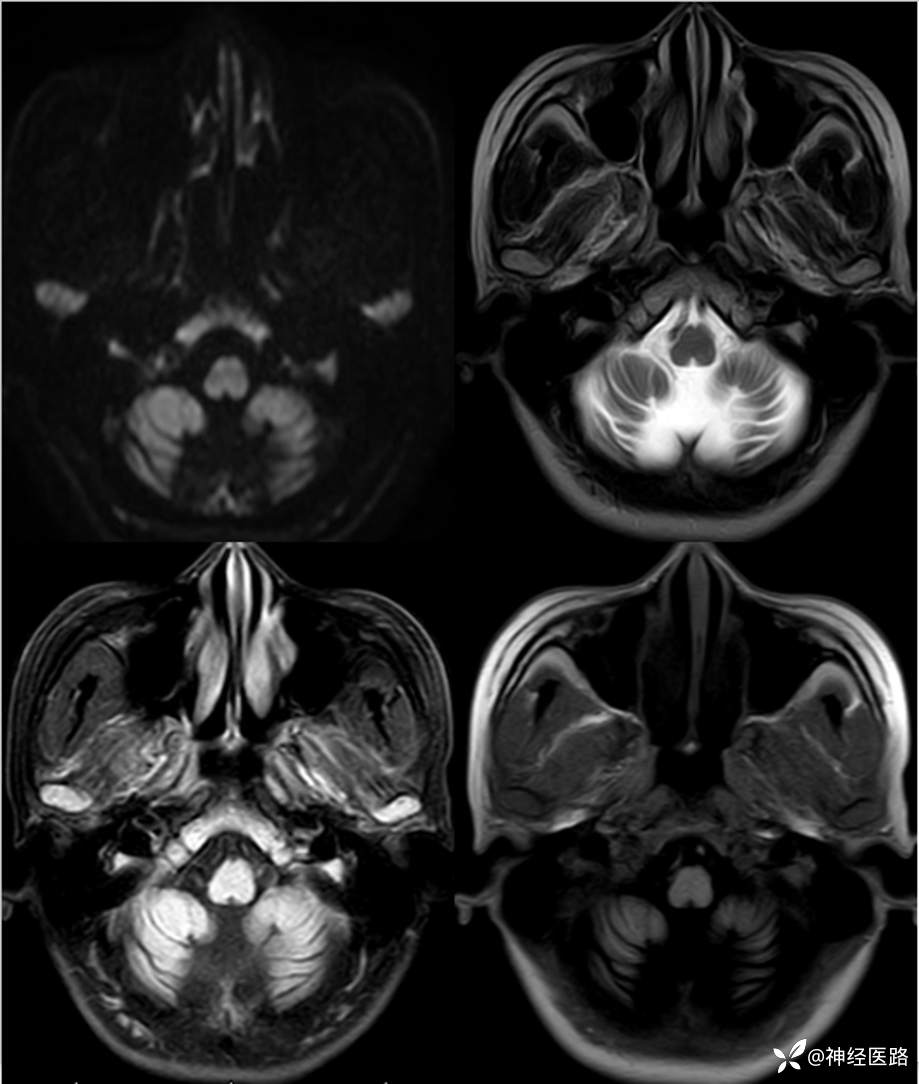

辅助检查:头部磁共振: 1.左侧额叶及右侧顶叶白质内高信号,请结合临床及相关检查。2.双侧小脑半球脑萎缩。3.部分颅骨信号增高。